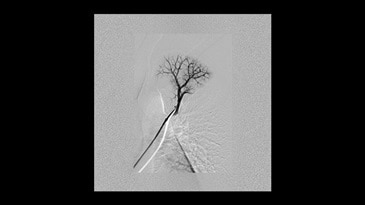

Klinik Görüntüler

-

Elde AVM